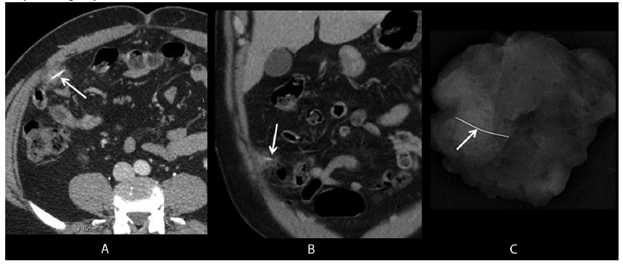

FIGURE. Axial and coronal images (A, B) from intravenous contrast-enhanced computed tomography show a wire grill-cleaning brush bristle in the omentum (arrows), surrounded by soft tissue stranding (inflammation); a specimen radiograph (C) from omental resection confirms complete foreign object retrieval (arrow).

Alternate Text: The figure above consists of three images. The first two are axial and coronal images from intravenous contrast-enhanced computed tomography showing a wire grill-cleaning brush bristle in the omentum, surrounded by soft tissue stranding (inflammation). The third image is a specimen radiograph from omental resection that confirms complete foreign object removal.

A man aged 50 years arrived at the ED with abdominal pain that had begun after eating steak at a backyard barbeque. Computed tomography (CT) scan of the abdomen and pelvis revealed a linear object extending through the wall of a loop of small intestine into the omentum (Figure). Laparotomy was performed to remove the foreign body, which appeared to be a wire bristle from a grill-cleaning brush. The patient fully recovered and was discharged the next day.

Severe abdominal pain was the chief symptom of the other patients, who were three men aged 31, 35, and 50 years (Table). These patients were evaluated primarily with intravenous contrast-enhanced CT of the abdomen and pelvis. In two patients, the wire bristle was noted lodged within the omentum adjacent to a loop of small intestine. In one patient, the wire bristle was located within the sigmoid colon, indenting the bladder. Two patients underwent emergency abdominal surgery to retrieve the foreign object and repair the intestine. In one patient, the wire had not perforated the intestine and was removed via colonoscopy.